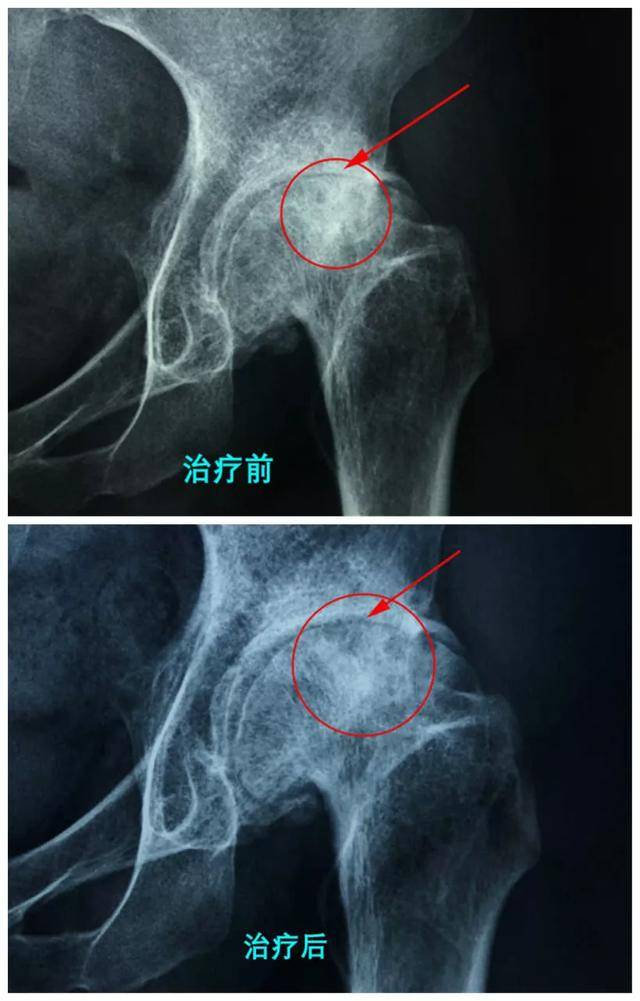

在衡水股骨头医院,众多成功案例证明了李氏三联疗法的有效性。这一疗法结合了骨内注射纯中药制剂、口服中药和外敷理疗,通过三位一体的方式,针对股骨头坏死患者开展个性化治疗。

股骨头坏死的保守治疗在三期患者中展现了令人鼓舞的效果,特别是在采用李氏三联疗法后,很多患者实现了明显的改善。该疗法通过结合三种方式——骨内注射纯中药制剂、口服中药和外敷理疗,有效缓解了病痛,提高了生活质量。这种方法的成功不仅在于其创新性,更在于能够针对个体不同的病情,为患者量身定制适合的治疗方案。近年来,越来越多的成功案例证明了这一疗法的可靠性,也推动了对保守治疗研究的重视。未来,医院将继续优化这一方案,为更多股骨头坏死患者提供更有效、更人性化的治疗选择。